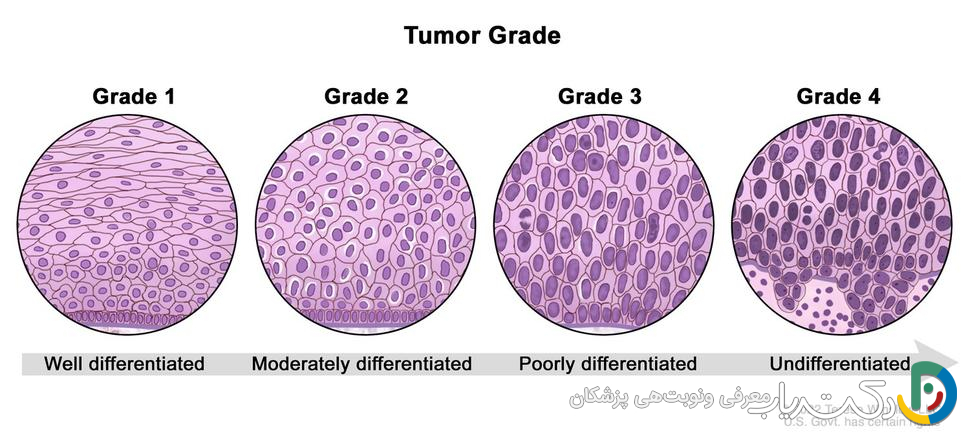

- تعیین توسط پاتولوژیست: گرید تومور مغزی توسط یک متخصص پاتولوژی و بر اساس ظاهر سلولهای تومور در زیر میکروسکوپ و همچنین ویژگیهای مولکولی آن مشخص میشود.

نمونه بافت تومور که طی جراحی یا بیوپسی سوزنی (مانند بیوپسی استریوتاکتیک) برداشته شده، به آزمایشگاه پاتولوژی فرستاده میشود. در آنجا، یک پزشک متخصص به نام پاتولوژیست، که در تشخیص بیماریها از طریق بررسی بافتها تخصص دارد، فرآیندی دقیق را آغاز میکند. بافت ابتدا پردازش شده، در بلوکهای پارافینی قرار گرفته و سپس با دستگاهی به نام میکروتوم به لایههای بسیار نازک برش داده میشود. این لایهها روی اسلایدهای شیشهای قرار گرفته و با رنگهای مخصوصی (مانند رنگآمیزی H&E) رنگآمیزی میشوند تا ساختارهای سلولی زیر میکروسکوپ قابل مشاهده باشند.

پاتولوژیست به دنبال ویژگیهای کلیدی میگردد که نشاندهنده میزان بدخیمی تومور هستند:

- آتیپی : میزان غیرطبیعی بودن ظاهر سلولها. پاتولوژیست بررسی میکند که آیا سلولها از نظر اندازه و شکل یکنواخت هستند یا ترکیبی آشفته از سلولهای بزرگ و کوچک با هستههای تیره و نامنظم. هرچه آتیپی بیشتر باشد، گرید تومور بالاتر است.

- میتوز : تعداد سلولهایی که در حال تقسیم فعال هستند. وجود “اشکال میتوزی” زیر میکروسکوپ نشاندهنده تکثیر سلولی است. تعداد بالای این اشکال، علامت رشد سریع و تهاجمی تومور است.

- تکثیر عروقی: تومورهای با رشد سریع برای تأمین اکسیژن و مواد مغذی خود، رگهای خونی جدیدی را به صورت غیرطبیعی ایجاد میکنند (فرآیندی به نام آنژیوژنز). این عروق جدید معمولاً ناقص و درهمتنیده هستند و وجودشان نشانه یک تومور با گرید بالا است.

- نکروز : وجود بافت مرده در مرکز تومور. وقتی تومور آنقدر سریع رشد میکند که خونرسانی به مرکز آن کافی نیست، سلولهای مرکزی میمیرند و ناحیه نکروز ایجاد میشود. نکروز، بهویژه نکروز شبهپالیسیدینگ (که در آن سلولهای تومور در اطراف ناحیه مرده حصار میکشند)، یکی از مشخصههای اصلی تومورهای گرید ۴ مانند گلیوبلاستوما است.

- ویژگیها: سلولهای این تومورها در زیر میکروسکوپ تقریباً طبیعی به نظر میرسند و رشد بسیار کندی دارند. آنها معمولاً مرزهای بسیار مشخصی دارند و مانند یک توده مجزا رشد میکنند، نه اینکه در بافت مغز نفوذ کنند.

- ویژگیها: سلولها کمی غیرطبیعی به نظر میرسند و رشد آهستهای دارند. تفاوت اصلی آنها با گرید ۱ در ماهیت نفوذی آنهاست. این تومورها مرزهای مشخصی ندارند و سلولهای تومور مانند ریشههای درخت به بافتهای سالم اطراف نفوذ میکنند. این ویژگی برداشتن کامل آنها با جراحی را بسیار دشوار یا غیرممکن میکند.

- ویژگیها: سلولهای این تومورها به وضوح غیرطبیعی هستند و به طور فعال در حال تقسیم شدن (میتوز بالا) میباشند. آنها رشد سریعی دارند و به طور تهاجمی به بافتهای سالم مغز نفوذ میکنند. زیر میکروسکوپ، شواهدی از آتیپی قابل توجه و فعالیت میتوزی بالا دیده میشود.

- ویژگیها: سلولها ظاهری بسیار غیرطبیعی و بدشکل دارند (آتیپی شدید). رشد آنها انفجاری و بسیار سریع است و به سرعت در سراسر مغز پخش میشوند. وجود نکروز (بافت مرده) و تکثیر عروقی از ویژگیهای بارز و مشخصه این تومورها در زیر میکروسکوپ است.